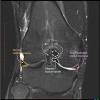

Knowing about knee anatomy can help people understand how knee arthritis develops and sometimes causes pain. View of the anatomical labels. Master leg and knee anatomy using our topic page. Mri knee anatomy cross patella sectional muscles sartorius femur surface epicondyle popliteus gastrocnemius muscle condyle atlas imaging body fascia. Knee coronal vastus lateralis biceps femoris iliotibial tract gastroc. Magnetic resonance imaging is particularly well suited for the medical evaluation of the musculoskeletal (msk) system including the knee it includes a very simplified approach to the mri imaging sequences and the thought process behind why we use those sequences. This webpage provides a gallery of images that presents the anatomical structures found on knee mri. This mri knee cross sectional anatomy tool is absolutely free to use. Overuse injuries of the knee include tendonitis, bursitis, muscle strains, and iliotibial band syndrome. (lateral) popliteal a + v. Free cross sectional anatomy of the knee based on mri : These are essential structures to evaluate in routine assessment of the knee on mri. Knee anatomy francesc malagelada jordi vega pau golanó the knee is the largest joint in the human body and one of the most complex from a functional point of view.

Want to learn more about it? Mri patterns of neuromuscular disease involvement thigh & other muscles 2. Click now to learn more about the bones, muscles, and soft tissues of these regions at leg and knee anatomy: 12 photos of the knee muscle anatomy mri. Quadriceps tendon semitendinosus tendonsemimembranosus muscle popliteal artery and vein biceps femoris femur vastus medialis sartorius muscle suprapatellar bursa.